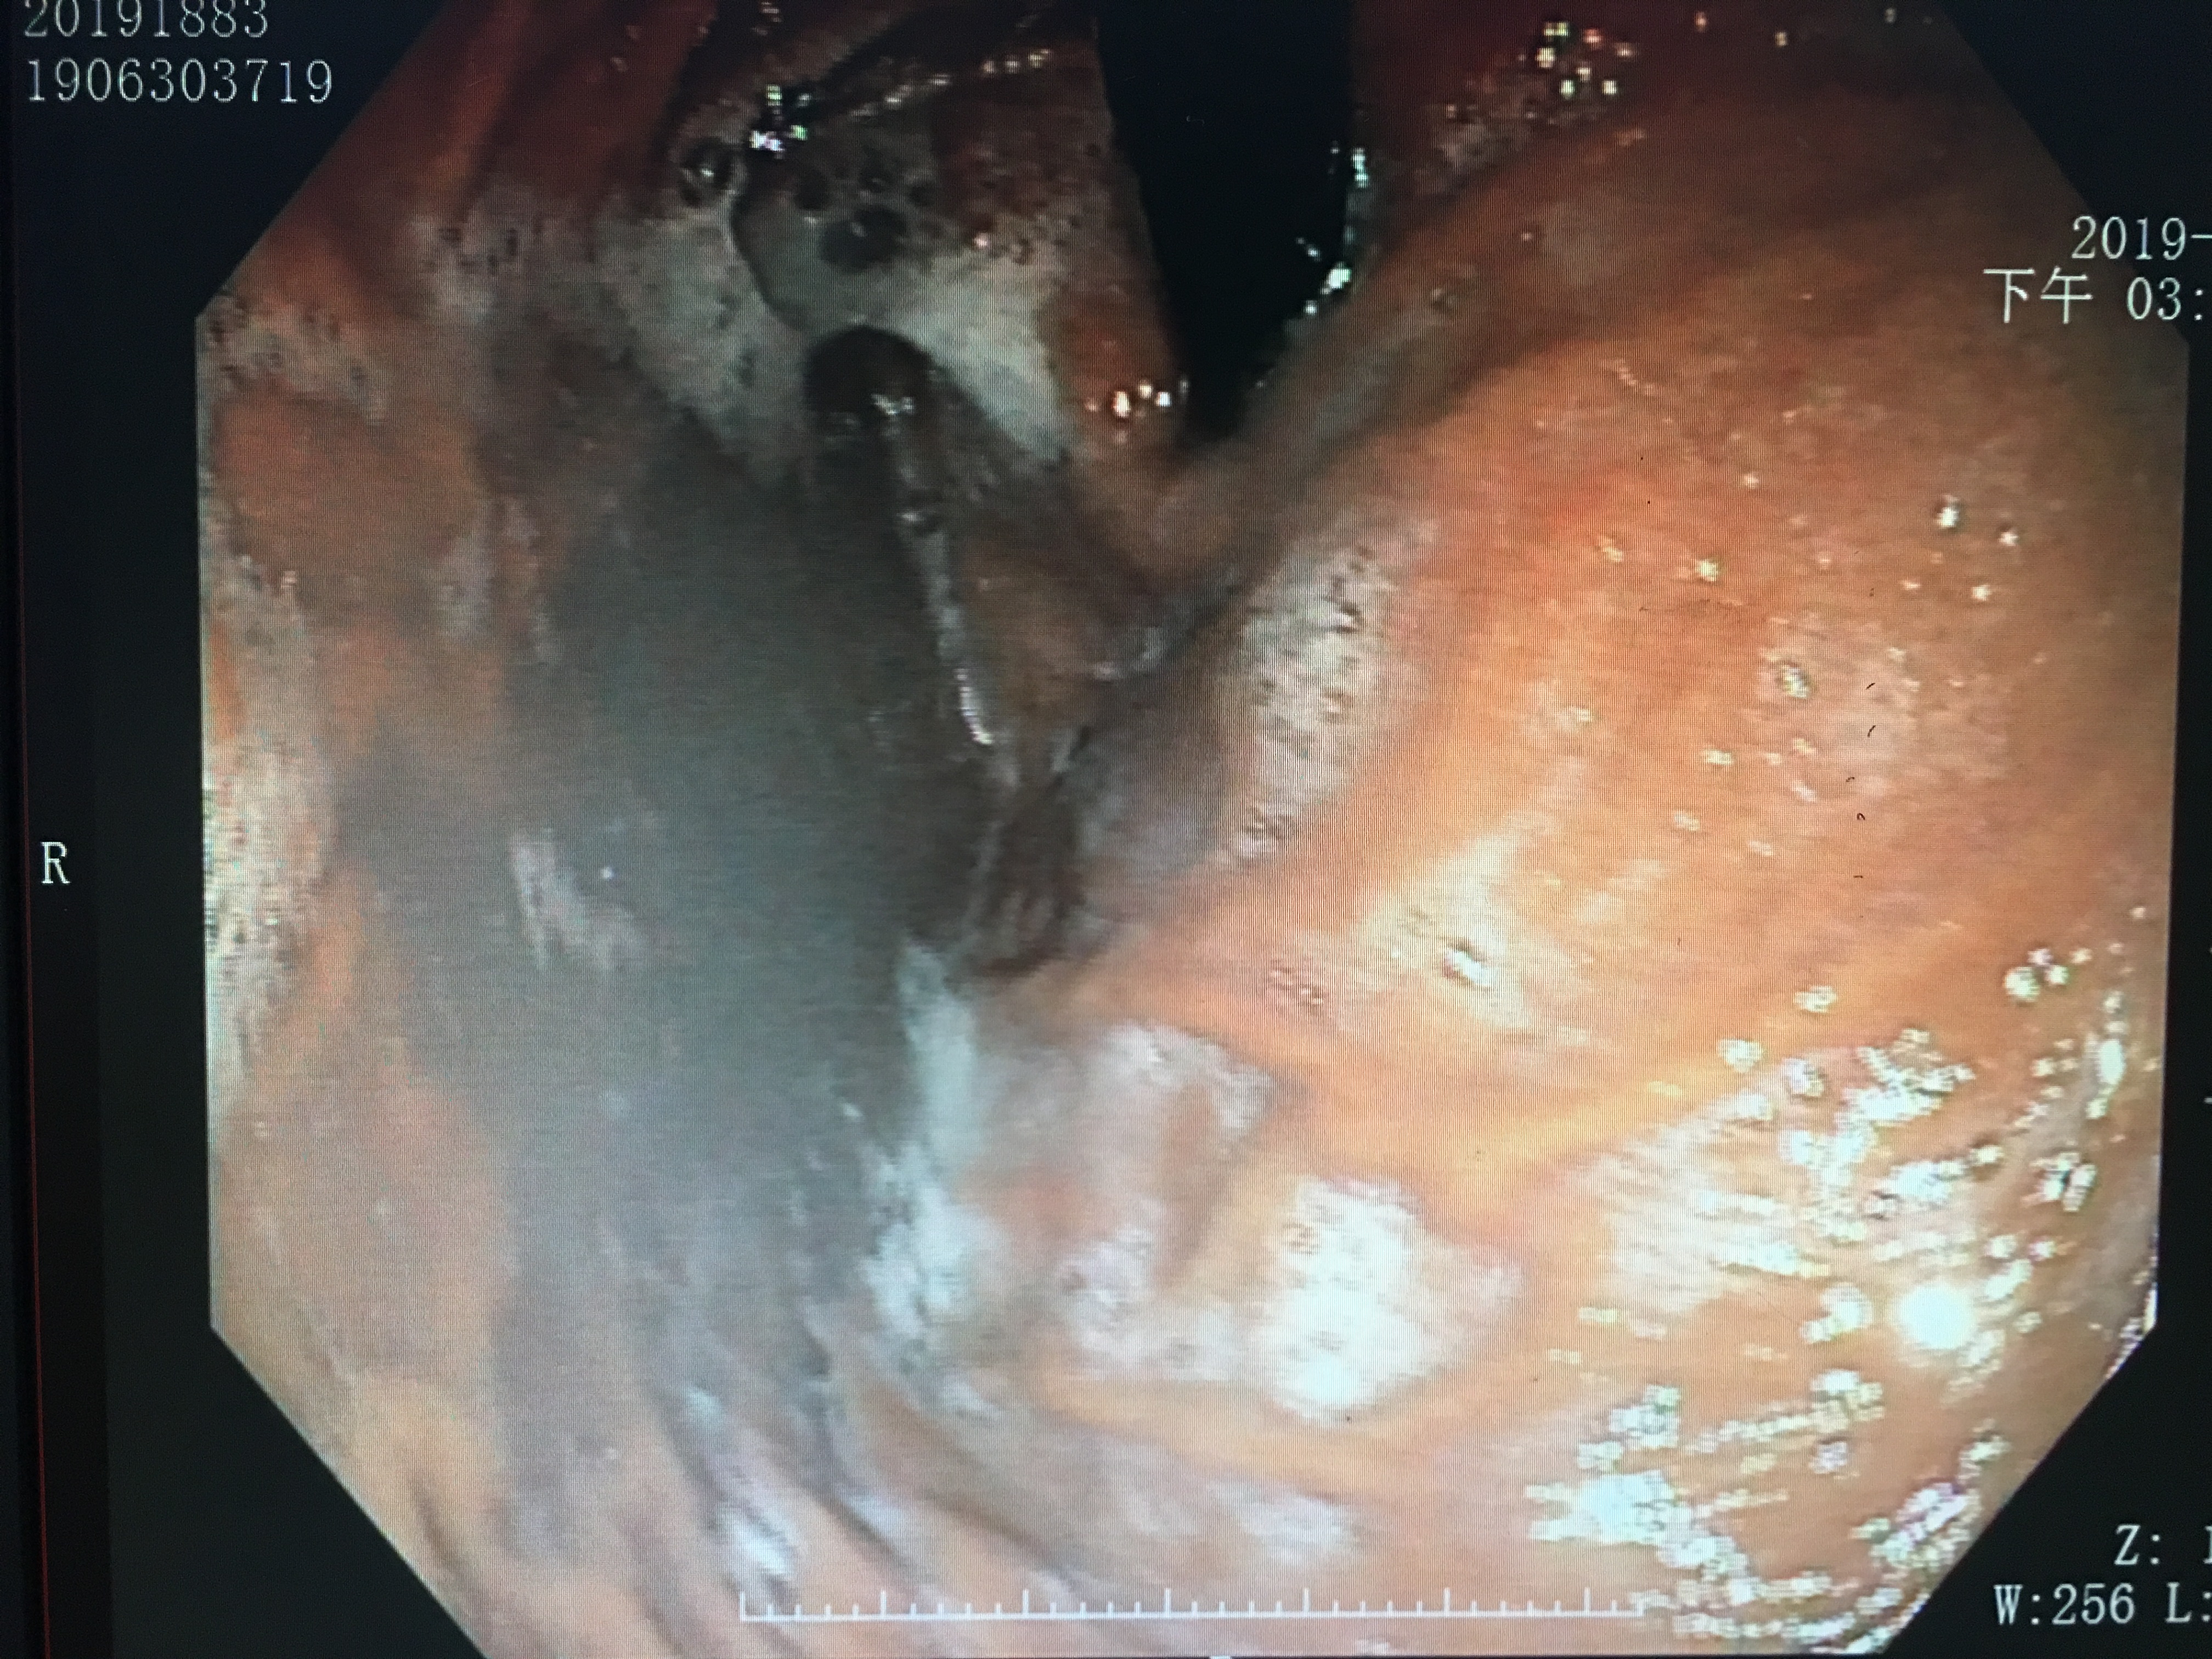

偷吃巧克力病人的胃镜视野

如果不是十分熟练经验丰富的医生,看到这样的景象,第一反应就是“上消化道出血?”。然而,图中却是一个偷吃巧克力患者的图像。请问,这样的景象,你想要的医生看出什么端倪?

吃进去的食物,经过口腔咀嚼以及胃部蠕动消化,会覆盖在胃粘膜的表面,当胃镜伸进去的时候,看到的就是“狼藉”战场。所以,胃镜之前严格禁食是很重要的。